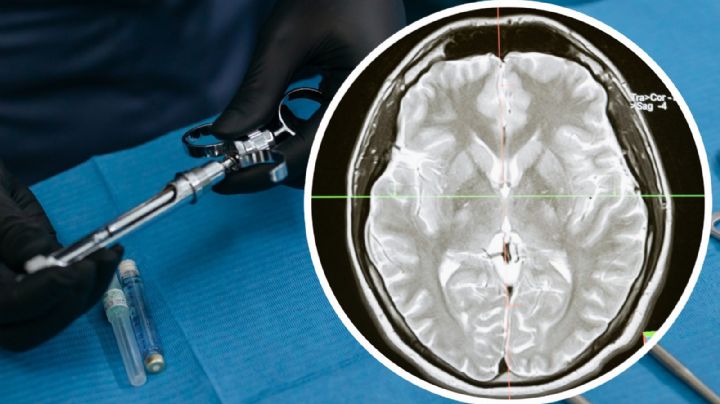

29/5/2023 | Las 570 personas sospechosas de haber contraído la enfermedad son mujeres que se realizaron una cirugía estética en dos clínicas particulares de Matamoros

27/5/2023 | Se tienen confirmados por la Secretaría de Salud, 23 casos, 9 de estadounidenses y 14 de mexicanos; hay un deceso

25/5/2023 | Cofepris analiza medicamentos y establecimientos involucrados; clínicas privadas fueron suspendidas desde el 13 de mayo

18/5/2023 | Piden a todas las personas que hayan sido intervenidas en las clínicas que fueron clausuradas, para que acudan ante las autoridades sanitarias

18/5/2023 | Varios ciudadanos estadounidenses que acudieron a realizarce cirugías a la ciudad de Matamotos, resultaron con infección y enfermaron gravemente; conoce cómo ocurre

17/5/2023 | Después del cierre de los nosocomios las autoridades sanitarias iniciaron la búsqueda de personas que estuvieron como pacientes en dichos establecimientos; hay cinco sospechosos en Texas y un muerto